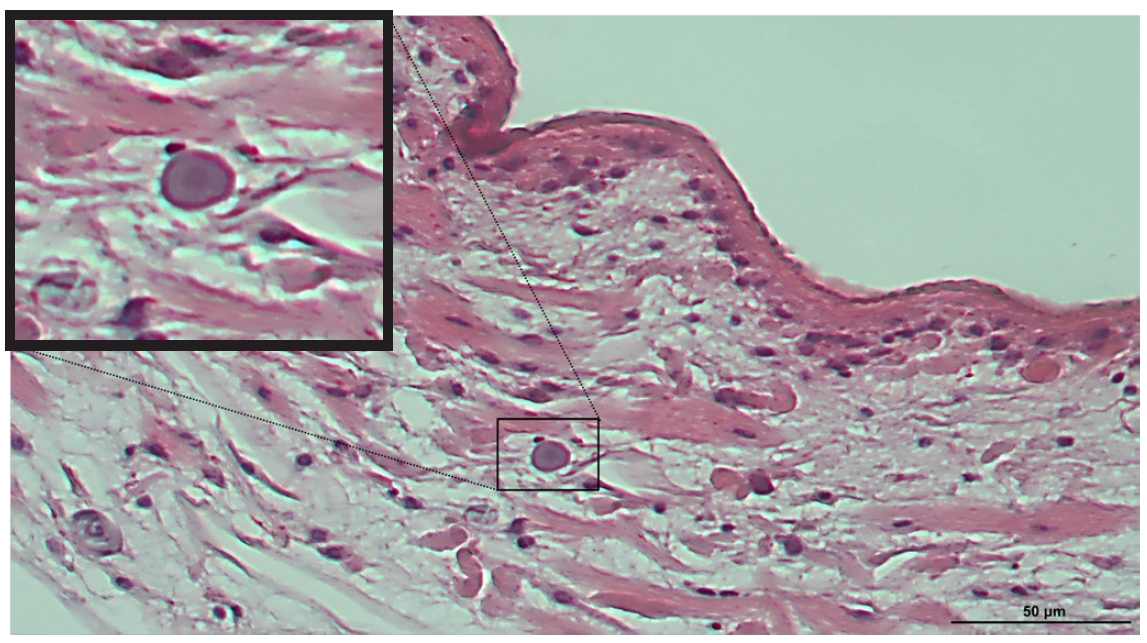

The parasite recovered during surgery was immediately fixed in formalin and embedded in paraffin for histopathological analysis. The transverse section showed a characteristic pattern of noncellular tegument, cellular subtegument, and parenchyma containing calcareous corpuscles are visible (

Fig. 1.Histopathological findings of Spirometra erinaceieuropaei in thigh tissue of the present case. The recovered parasite was fixed in formalin, embedded in paraffin, sectioned, and stained with hematoxylin and eosin. Characteristic basophilic calcareous corpuscles were clearly observed within the parasite and are also shown in the magnified view. Scale bar=50 μm

S. erinaceieuropaei. Calcareous corpuscles are characteristic structures of cestode larvae and serve as an important diagnostic marker for identifying

Spirometra spp. In the present case, these structures were clearly observed within the larval tissue (

Fig. 1).